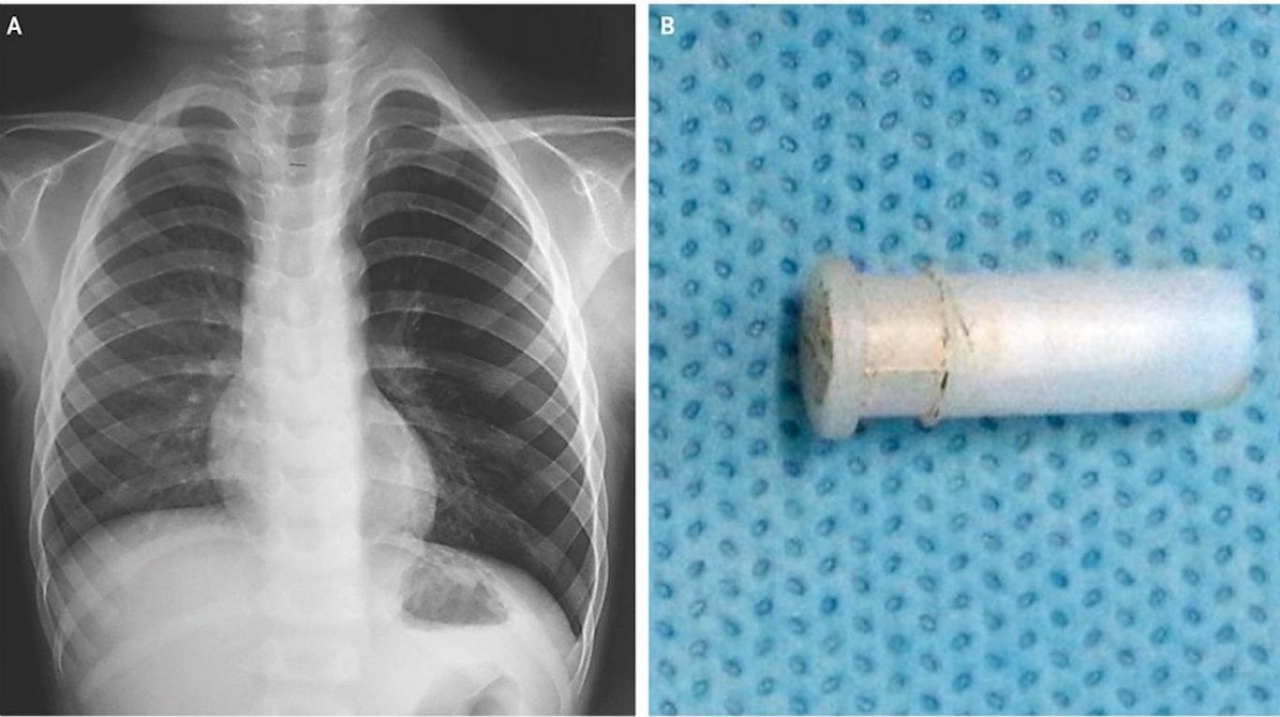

Una radiografía del tórax reveló rápidamente que su pulmón izquierdo estaba “hiperinflado”, lo que podía ser causado por un bloqueo en el paso del aire a los pulmones o por afecciones médicas que podían incluir desde asma hasta fibrosis quística, según un informe de Mayo Clinic.

Inmediatamente después, los médicos procedieron a realizar una broncoscopia, tras lo cual pudieron extraer un "objeto misterioso”. Se trata efectivamente de un silbato de juguete. Los padres del niño recordaron luego del hallazgo que su hijo había estado jugando con un silbato antes de que comenzara a toser.

Al día siguiente, una nueva radiografía demostró que el pulmón izquierdo del chico se había “desinflado” y había vuelto a la normalidad.